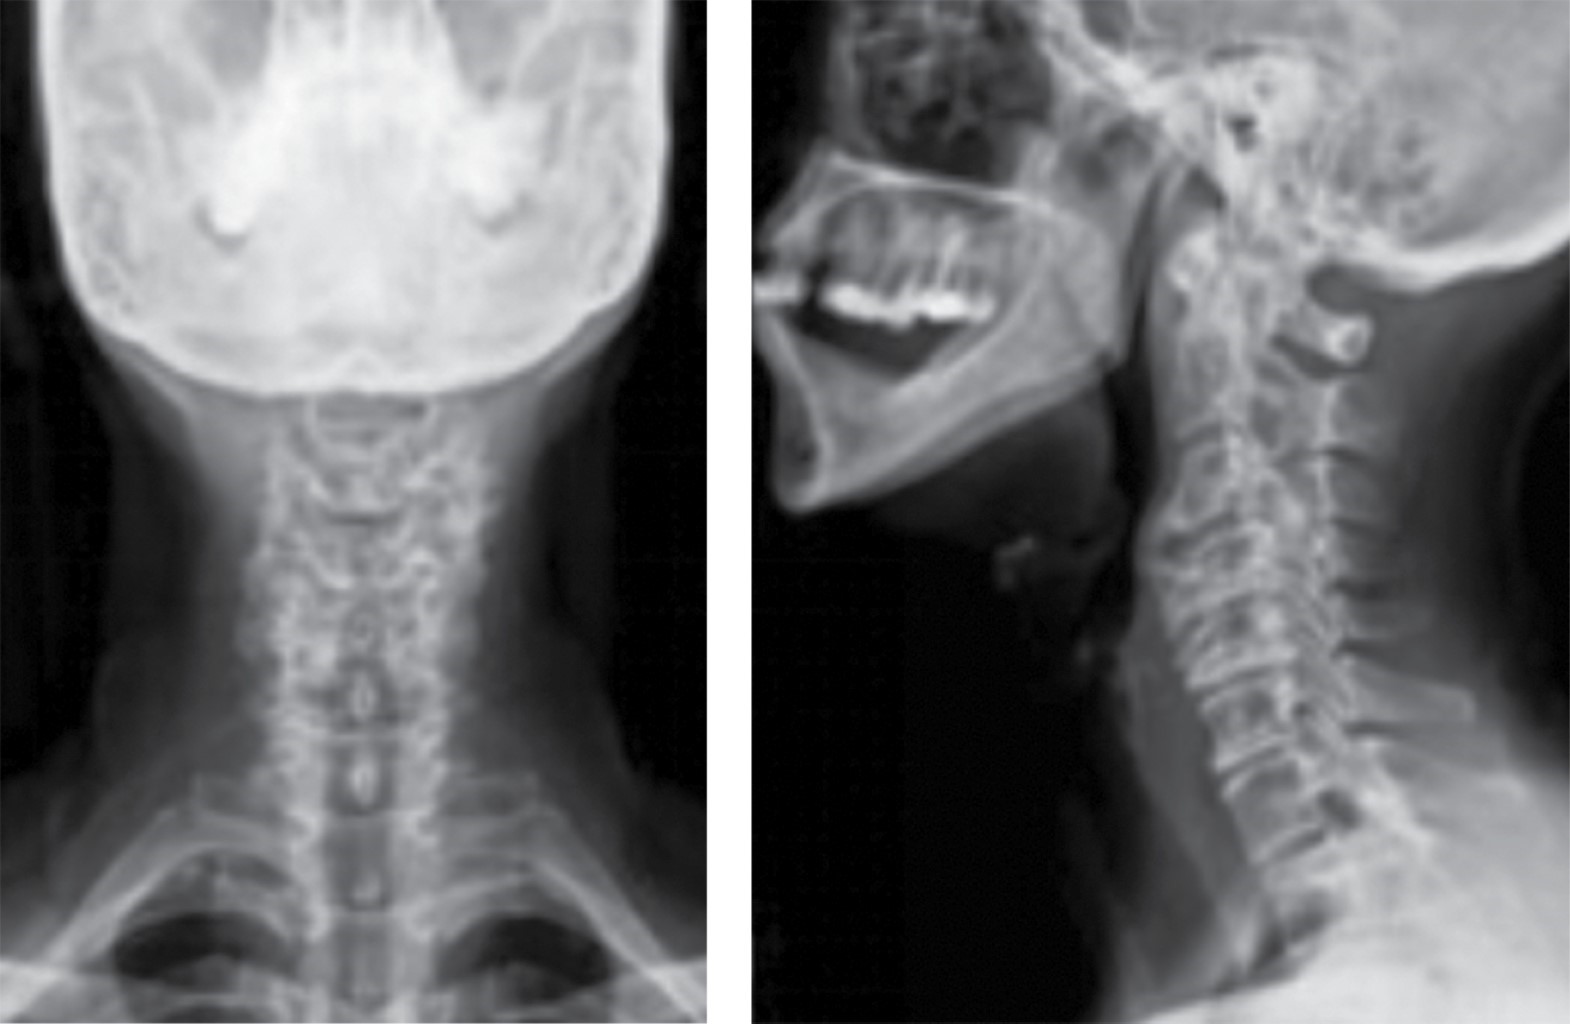

En las distintas revisiones los pacientes mostraron una mejoría tanto de la lordosis cervical como de la altura discal (Figura 1) en comparación con los resultados preoperatorios (Figura 2). Se encontraron estudios realizados con placa e injerto, mejoría en el ángulo de Cobb y en la altura intersomática (p = 0.038 y p = 0.0004, respectivamente).10 En estudios que evaluaron el resultado radiográfico con relación a la lordosis global no hubo diferencia estadísticamente significativa entre usar placa-injerto, placa-caja o caja de PEEK, (p = 0.003, p = 0.006 y p = 0.001, respectivamente), lo cual nos permite efectuar un abordaje menos invasivo con resultados satisfactorios. Shan-Jin Wang y colaboradores demostraron en su estudio realizado en cuatro niveles con cajas de PEEK, que el ángulo de Cobb y la altura intersomática mejoraron de manera postoperatoria con una significancia clínica con un valor de p = 0.019 y p ≤ 0.01, respectivamente,11 lo que demuestra que se puede obtener un resultado radiográfico satisfactorio independientemente de la cantidad de niveles operados.

Figura 1

Figura 2